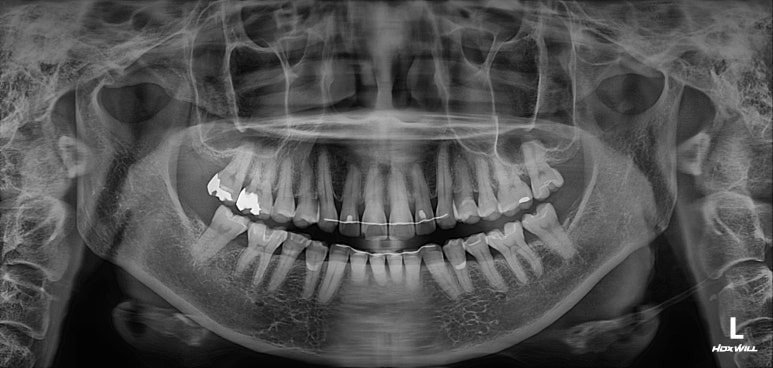

엑스레이를 찍는 이유는 잇몸이 건강한지를 확인하기 위함입니다.

50대 여성분임에도 불구하고 충분히 건강한 잇몸상태를 확인할 수 있었습니다.

그러면.. 교정치료가 가능하다는 뜻입니다.

치아의 뿌리 상태를 확인하기 위한 방사선 사진 촬영 필수!

교정을 하기 전에 무조건 위아래 앞니의 뿌리길이를 체크해야 합니다.

아무래도.. 성인교정의 대부분은 삐뚤어진 앞니 배열의 개선이지요?

그러면 앞니의 움직임이 다소 많을 것이기 때문에, 교정하기에 적합한 뿌리 길이를 갖고 있는지 확인해야합니다.

그런 면에서 이번 환자분은 당연히 합격!

마지막으로 파노라마 엑스레이를 찍고 마무리하였습니다.

보시다시피 모든 치아가 뿌리가 나란하게끔 교정이 마무리 된 것은 아닙니다만, 생리적으로 적절한 교합을 형성하였고 가장 눈에띄는 앞니는 배열을 가지런히 맞추어 내었습니다.

치과용 파노라마 엑스레이를 보았을 때, 특별히 잇몸이 안좋아진 치아도 보이지 않았으며 향상된 치아배열로 인해 구강위생관리 또한 향상되어 있다는 생각이 절로 들었습니다.